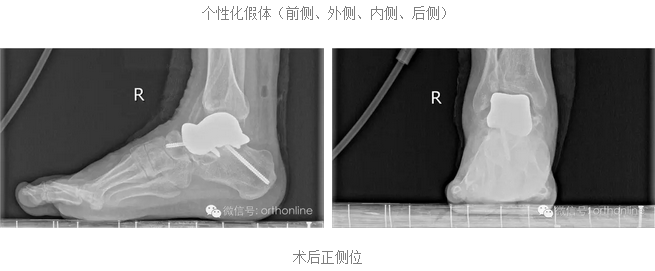

假体个性化特性更为明显:

假体制作完全忠实于患者个体的解剖结构,术前将健侧的骨性解剖数据进行镜像处理,获得个性化假体数据源;3D打印完成后再将假体扫描,与数据源进行耦合对照检测;假体植入后扫描患肢,检测与数据源耦合性能;

根据距骨不同部位力学需求,选用力学性能匹配的金属材料和打印方式,完成力学性能的个体化。突破踝关节置换的禁忌:

塌陷性距骨坏死一直是踝关节假体置换的绝对禁忌症,该假体打破了常规,为塌陷性距骨坏死提供了非常好的选择。